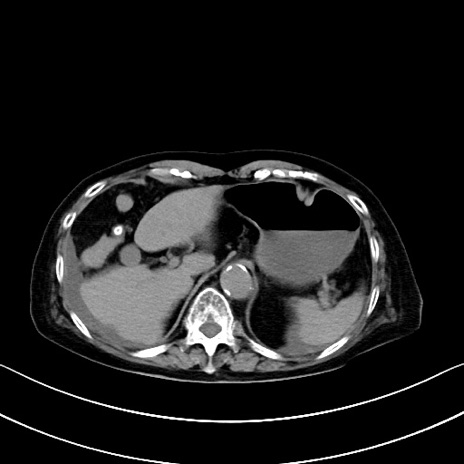

症例40(横断像)他院1日前

横断像

他院CT